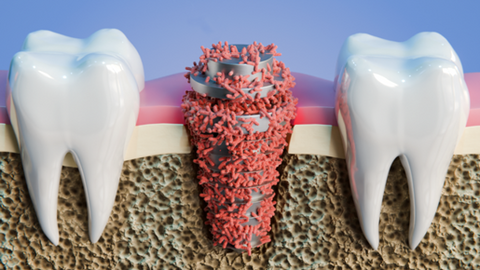

Projet Interreg SAFE

Un projet transfrontalier pour rendre les implants médicaux plus sûrs et plus fiables.

Publié le 06/10/2025

Projet Interreg ANTIRESI

Les matériaux au service de la lutte contre l’antibiorésistance.

Materialen in de strijd tegen antibioticaresistentie.

Publié le 06/10/2025